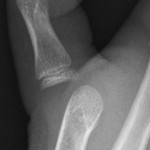

Fingertip Fractures

- With crush injuries of the tip of the finger, soft tissue injury is more important than bony injury

- Generally, fractures of the tip of the distal phalanx require no treatment other than symptomatic buddy strapping or an aluminium finger splint

- However, if there is associated nail bed injury or pulp laceration, the fracture is a compound fracture and an opinion should be sought from the Plastic Surgery team

Antibiotics may be needed. Refer to Antibiotics – ED Guideline

- Isolated dislocations are rare in children because their ligaments are stronger than bone, and trauma sufficient to induce dislocation in adults invariably results in bony fracture in children – refer to Fractures - Hand guideline.

Thumb dislocation

|